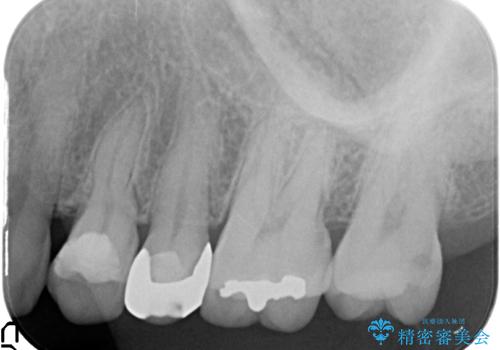

- 左上の奥歯がズキズキ痛むので診て欲しいといらっしゃった方の症例です。

診査の結果左上5、6番の歯が痛みの原因であり、神経の保存が難しかったため根管治療を行いました。

痛みの消失を確認後、オールセラミッククラウンによる補綴を行いました。